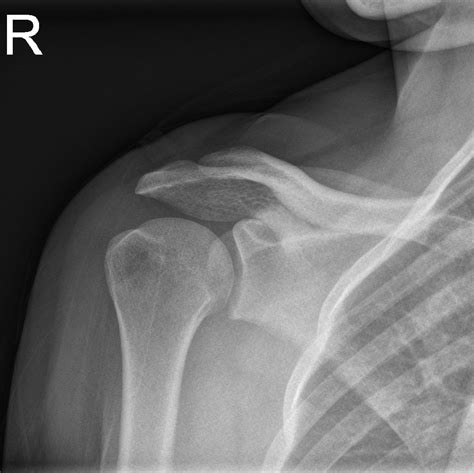

Understanding the significance of a shoulder X-ray normal result is crucial for both medical professionals and patients. A shoulder X-ray is a common diagnostic tool used to evaluate the bones, joints, and surrounding soft tissues of the shoulder. This imaging technique helps identify fractures, dislocations, arthritis, and other abnormalities. However, interpreting a shoulder X-ray normal result requires a thorough understanding of the anatomy and potential pathologies that can affect the shoulder.

The shoulder is a complex joint composed of several bones, muscles, and ligaments. The primary bones involved are the humerus (upper arm bone), scapula (shoulder blade), and clavicle (collarbone). The shoulder joint is a ball-and-socket joint, allowing for a wide range of motion. The rotator cuff, a group of muscles and tendons, plays a crucial role in stabilizing the shoulder and enabling movement.

A shoulder X-ray is a non-invasive imaging test that uses electromagnetic radiation to produce images of the shoulder joint and surrounding structures. This test is often the first step in diagnosing shoulder pain or injury. The X-ray can reveal fractures, dislocations, arthritis, and other bone abnormalities. However, it may not always show soft tissue injuries, such as tears in the rotator cuff or ligaments.

When a shoulder X-ray normal result is reported, it means that the X-ray images do not show any visible abnormalities in the bones or joints. This can be reassuring for patients experiencing shoulder pain, as it indicates that there are no obvious fractures or dislocations. However, it is important to note that a normal X-ray does not rule out all possible causes of shoulder pain.